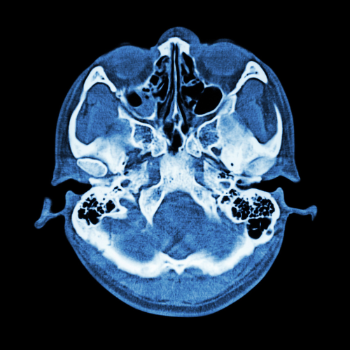

After a series of tests and consultations, Rakesh was diagnosed with a complex skull base tumor. It was a diagnosis that carried with it a cocktail of emotions fear, uncertainty, and desperation. The skull base, a delicate and intricate area of the human anatomy, houses vital nerves and blood vessels, which made surgical intervention both necessary and perilous.

Enter Dr. Kavita Menon, a renowned brain and spine surgeon specializing in skull base surgery. With years of experience and a compassionate approach, Dr. Menon has dedicated her life to addressing the unique challenges faced by individuals like Rakesh. Skull base surgery, a highly specialized field, is designed to tackle tumors and abnormalities located at the base of the skull, offering hope and healing to patients who might otherwise face a grim prognosis.

The major problem faced by Rakesh, and indeed many others in similar situations, is the risk of neurological damage and the potential loss of quality of life. This is where the expertise of specialists like Dr. Menon comes into play. Utilizing cutting-edge technology and minimally invasive techniques, skull base surgery addresses these concerns by safely removing tumors while preserving crucial functions.